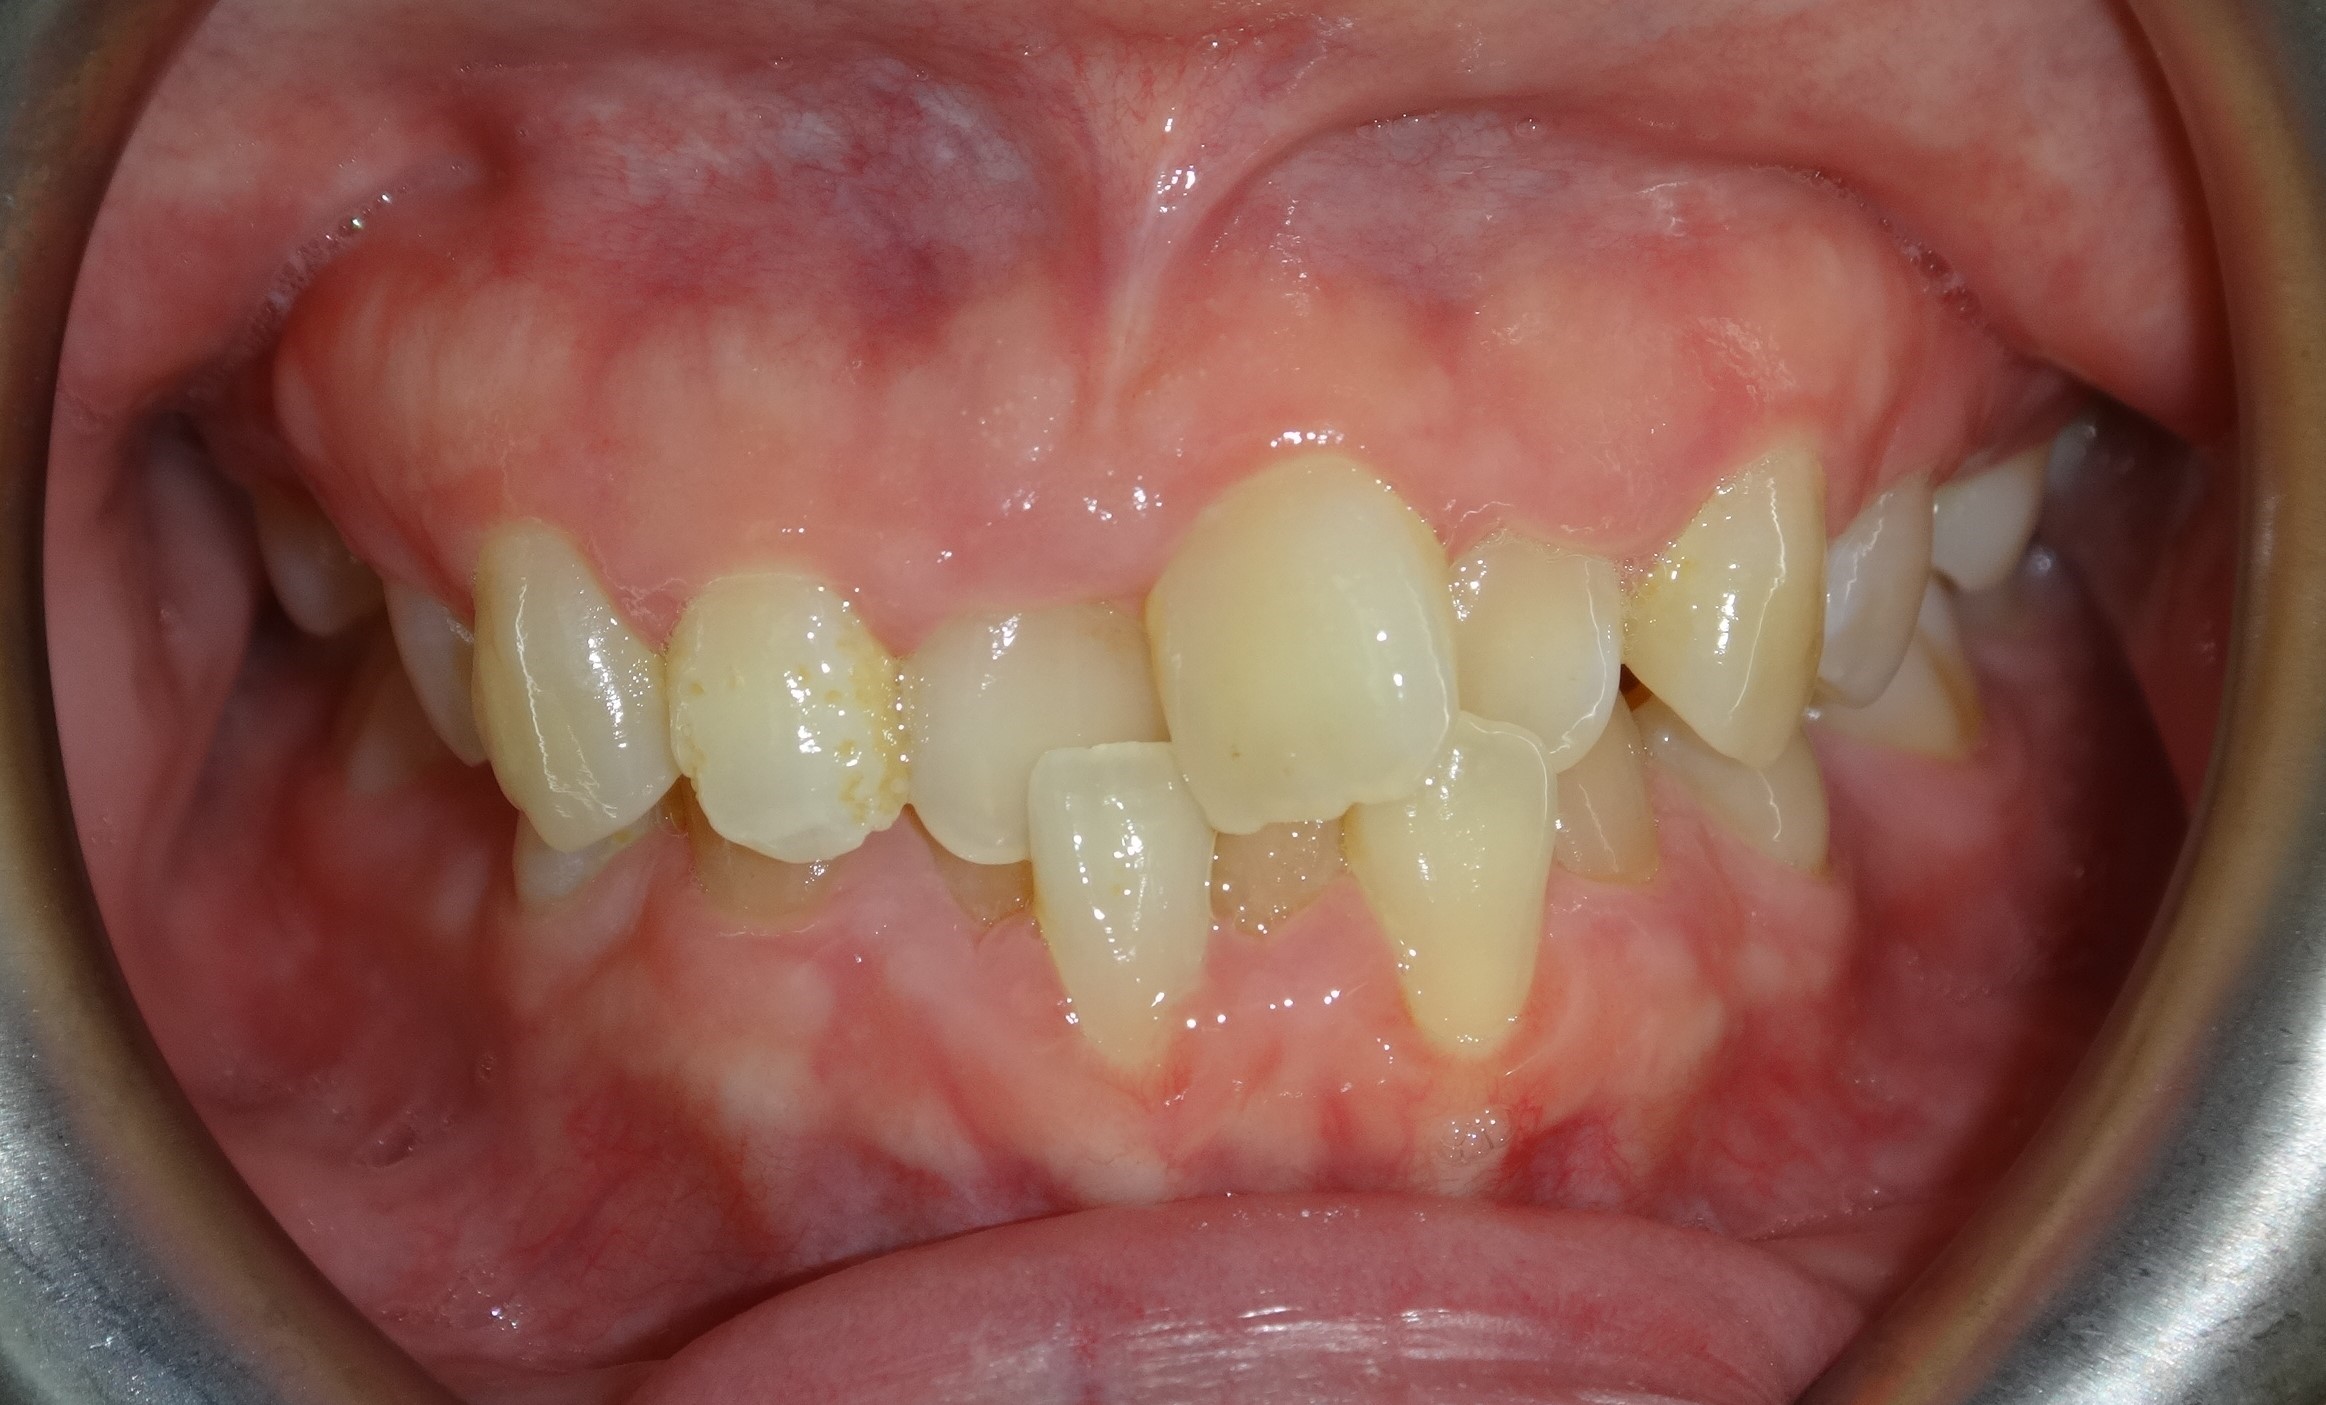

不拔牙案例 首頁 案例分享 齒顎矯正 不拔牙案例 - 矯正不拔牙案例 - 年紀:27歲 治療方式:隱適美隱形矯正 時間:34個月 主訴:前牙錯咬、排列不整 矯正前 矯正後 矯正前 矯正後 矯正前 矯正後 聲明:本所療程皆由專業醫生評估後,依照個人口腔狀況進行治療。因每位患者個別狀況不同,術後狀況也不盡相同,需親來本所由醫生評估。